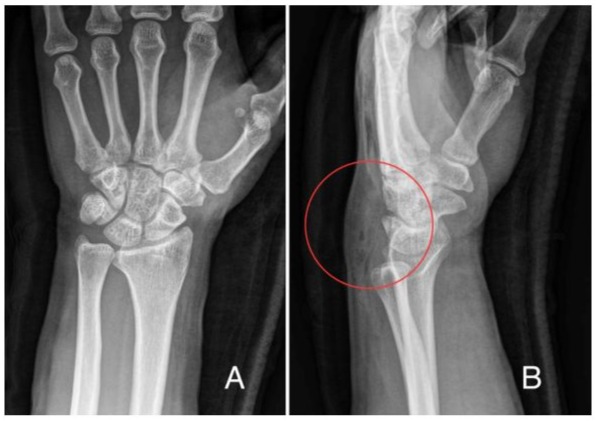

A 36-year-old male patient visited our clinic, complaining of right wrist pain. He was an office worker and had no medical history on his right wrist. He rode his bicycle and bumped into a car which was parked in a street one day before the visit. The handle of the bicycle hit his palm quite hard making his wrist hyperextended. Physical examination revealed moderate tenderness and swelling on the dorsal aspect of the wrist. Active motion, especially dorsiflexion was limited due to pain. However, the plain radiographs at initial visit showed no definite fracture at his right wrist but soft tissue swelling of the wrist dorsum (Figure 1). We diagnosed it as a wrist sprain and put a short arm splint on his right wrist. We checked plain radiographs again 2 weeks after the injury. As we confirmed that there was no fracture identified on the plain radiographs, we removed the splint and let him return to his daily activity. However, he visited our clinic 5 weeks after injury, complaining of inability to actively extend his right thumb. Physical examination showed loss of active extension of thumb interphalangeal joint. On MRI, an EPL tendon was ruptured around the Lister’s tubercle (Figure 2), although there was no signal change of distal radius or other carpal bones, suggesting a bone contusion or a microfracture. The distal stump was identified around the 1st carpo-metacarpal joint, and the proximal stump was not definitely delineated. Abundant fluid collection was observed around the ruptured tendon ends (Figure 2).

Figure 1: The plain radiographs at initial visit showed no definite fracture at both wrists (A) Postero-anterior (B) Lateral (red circle): Soft tissue swelling of the wrist dorsum was observed.